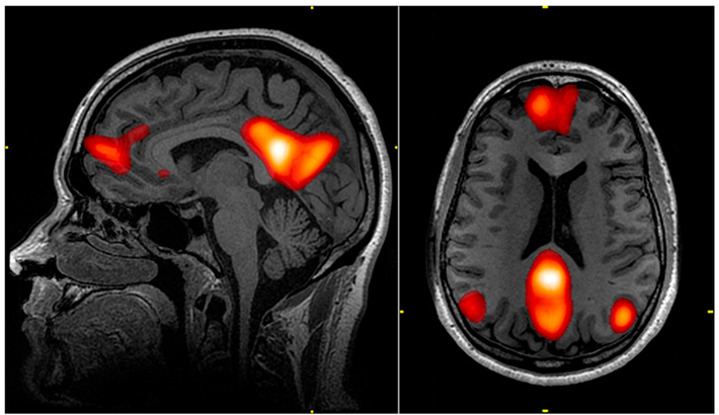

最後に取り上げるのは道徳的判断です。何が正しいかという判断は非常に難しいものなのですが、道徳的判断に関係する脳領域もいくつかあります。何かをルールベースで判断するような課題(未成年の飲酒は法律違反である、など)では、外側前頭前野と外側頭頂葉が活性化するのですが、個人的判断(村のみんなを守るために自分の子供を殺すことの是非、など)では内側前頭前野と内側頭頂葉が活性化することが報告されています(Greene et al., 2001)。内側前頭前野と内側頭頂葉を結ぶネットワークはデフォルトモードネットワークと呼ばれ主観的な自己感覚に関わっています。道徳的判断はそう考えると主観的な側面もあるのなのかなと思ったりもします。

デフォルトモードネットワーク